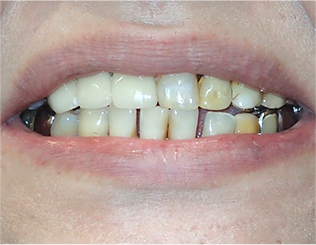

- ブリッジ 症例写真 B-0113FZC8本 女性モニターの方です。

この方は古い差し歯の黄ばみを治したいとご来院されました。 奥歯に欠損もありましたので、前歯はジルコニアセラミック、奥はジルコニアブリッジで治しました。 1回の治療で前歯も奥歯も同時進行で治療します。 1回目の治療時に仮歯を入れますので、すぐに見た目が気にならなくなります。 治療回数は5回でした。